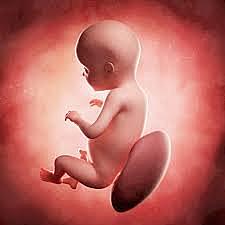

• Semana 20

35

Semana 20

el lanugo cubre todo el cuerpo

aparecen las cejas y las pestañas

aparecen las uñas en pies y manos

el bebé es más activo con mayor desarrollo muscular

la madre puede sentir al bebé moviéndose

los latidos cardíacos fetales se pueden escuchar con un estetoscopio